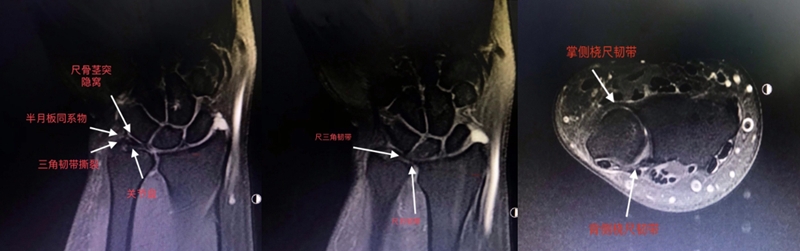

三角纤维软骨复合体(TFCC)是手腕最重要的纤维软骨-韧带复合结构,位于腕关节尺侧,分隔尺腕和远侧尺桡关节。常被称为是腕关节的“半月板”。

TFCC由以下韧带和纤维软骨组成:固有三角纤维软骨(TFC)、背侧桡尺韧带(DRUL)、掌侧尺韧带(PRUL)、尺三角韧带(UTL)、尺月韧带(ULL)、月三角韧带(LTL)、尺侧腕伸肌腱(ECU)鞘、尺侧副韧带(UCL)及半月板类似体(MH)。

ⅠA,TFCC中心穿孔,A、B三角软骨盘正常弓形低信号缺损;C轴位显示三角软骨盘中心的高信号区与D关节镜一致

ⅠB,TFCC尺侧撕裂;TFC尺侧附着处信号增高

ⅠC,尺三角韧带撕裂

ⅠD,TFC桡侧撕裂,桡侧附着处及桡尺关节处信号增高

ⅡA,TFC局部变薄,但结构完整

ⅡB,TFC局部变薄,但结构完整,月骨软骨厚薄不均

ⅡC,TFC中心撕裂,月骨软化,月三角韧带完整

ⅡD,TFC中心撕裂,月骨软化,月三角韧带缺如

图30 ⅡE,TFC中心撕裂,月骨、尺骨软骨软化,月三角韧带缺如,桡尺关节骨质增生